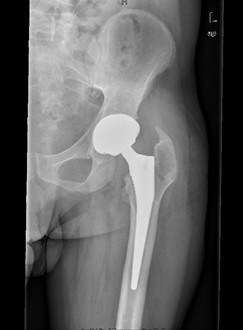

诊断:左股骨头股骨颈粉碎性骨折切开复位内固定术后坏死 治疗:择期行关节置换术